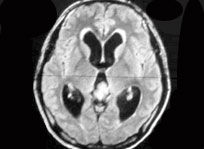

腦脊液為無色透明的液體,充滿在各腦室、蛛網膜下腔和脊髓中央管內。

.腦脊液具有保護和營養腦及脊髓的作用。正常腦脊液具有一定的化學成分和壓力,對維持顱壓的相對穩定有重要作用。患中樞神經系統疾病時,常常要作腰椎穿刺吸取腦脊液檢查,以協助診斷。如果腦脊液產生過多,或循環通路受阻,均可導致顱內壓升高。